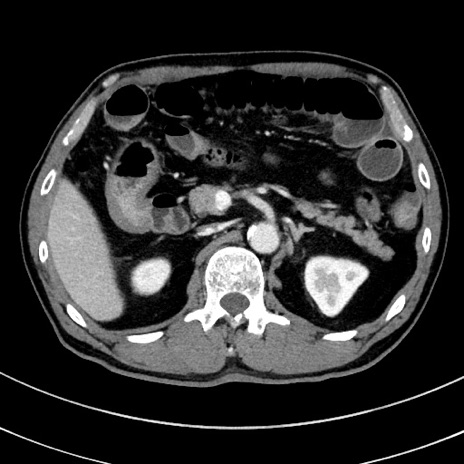

症例8(横断像)

【症例】 60歳代男性

【主訴】 黒色吐物

【現病歴】 4日前から嘔気自覚、2日前の朝食後にも嘔気あり、自分で手で嘔吐反射起こし嘔吐したところ血が混ざっていたため受診。

【既往歴】 5年前汎発性腹膜炎を伴う急性虫垂炎で手術、高血圧、前立腺肥大症、高脂血症

【身体所見】 腹部正中に手術癩痕あり 腹部平坦・軟圧痛なし膨満感あり

【データ】WBC 8400、CRP 4.54